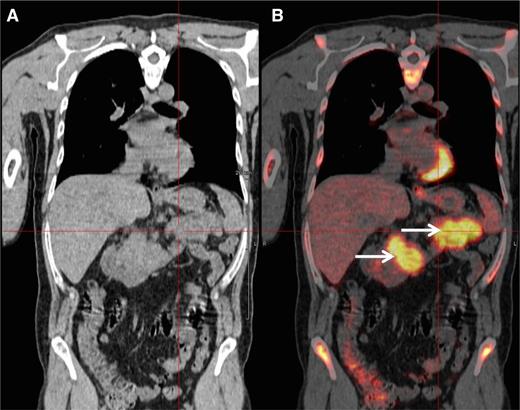

A 48-year-old man was diagnosed with IgG-κ myeloma in 2013. The patient presented with myeloma-related anemia and bone lesions. The prognostic analysis did not show the presence of high-risk FISH abnormalities, but a stage 3 ISS and an elevated LDH level. At this time no extramedullary disease was detected using PET-CT and MRI. The patient received induction therapy (3 courses of bortezomib-lenalidomide-dexamethasone), intensification (high-dose melphalan/ASCT), consolidation (2 courses bortezomib-lenalidomide-dexamethasone), and lenalidomide maintenance (IFM/DFCI2009 clinical trial). After completion of this sequence, the patient achieved a stringent CR (sCR). During cycle 10 of the maintenance therapy, the patient presented with epigastric abdominal pain and vomiting. Biochemistry tests showed elevated lipase levels, and a CT scan revealed a homogeneous hypertrophy of the pancreas. At the same time, the patient did not display any clinical criteria of myeloma relapse: he had normal blood cell counts and no CRAB symptoms. The bone marrow aspirate did not show abnormal plasmacytosis, and there was no M-spike in the serum electrophoresis. However, serum and urine κ free light-chain levels were elevated (250 mg/L and 300 mg/24 hours, respectively) confirming a light-chain escape. A PET-CT scan revealed an intense fluorodeoxyglucose (FDG) avidity of the pancreas (maximum standard uptake value = 11; Figure 2). The biopsy of the pancreas confirmed the infiltration by clonal PCs. Genetic and molecular analyses were performed and revealed no 17p deletion, no 14q32 recurrent translocation, and no BRAF mutation. The patient started pomalidomide-cyclophosphamide-dexamethasone therapy and achieved a CR according to standard criteria, including PET-CT. After 6 cycles, the patient is still continuing therapy.

PET-CT scan. PET-CT scan (A) demonstrating increased FDG avidity of the pancreas (B, arrows) in an MM patient who developed epigastric pain during maintenance therapy.